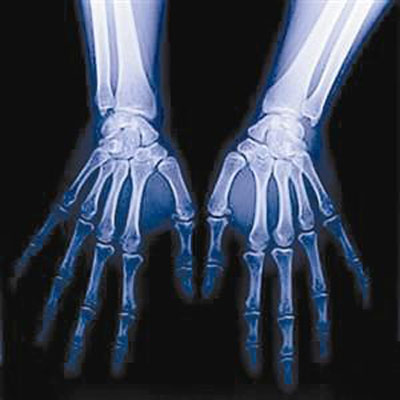

一张手部X光片 就能看孩子未来有多高

只要拍一张手掌X光片,就能精确评估孩子的身高还能不能长、还能长几厘米、最终能长到多少厘米,并针对不同情况制定科学的增高处方。

所谓X线计测法,就是通过X线拍一张手部骨龄片,评估腕骨骨化中心的数目、大小、相互之间的位置关系,与实际年龄、身高的差异性,并结合父母的身高,从而推断孩子成年身高。同时,通过诊断指导合理饮食、运动、睡眠等,制定科学的增高处方,还给孩子绘制生长曲线图谱,家长可以依据图谱来监测孩子身高增长速度,如果在正常范围内,只需要定期随访即可,如偏离正常轨道,就需要及时就诊,必要时进一步检查,甚至生长激素治疗。